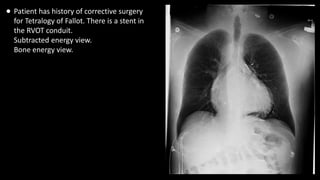

• Patient has history of corrective surgery

for Tetralogy of Fallot. There is a stent in

the RVOT conduit.

Subtracted energy view.

Bone energy view.